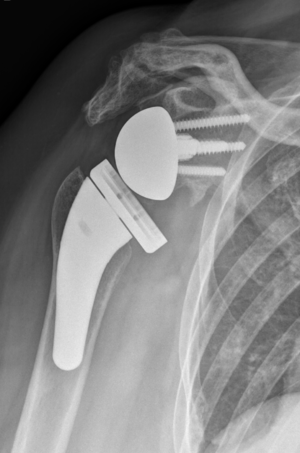

Acute proximal humerus fracture

Reverse shoulder arthroplasty is a more reliable treatment than hemiarthroplasty for complex proximal humerus fractures at least in elderly patients because its functional outcomes appear to depend less on tuberosity healing and rotator cuff integrity (Figure).[90]

Reverse shoulder athroplasty for fracture. Frontal, axial and lateral Lamy radiographs after a reverse total shoulder implant. Note the lower positioning of the glenoid baseplate, the satisfactory reconstruction of the tuberosities, and the absence of cement at the autograft level.